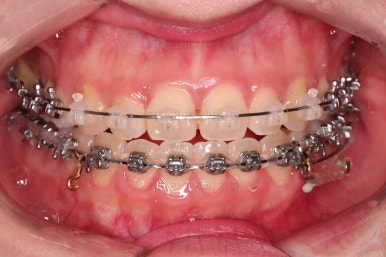

이번 환자분이 선택하신 장치는 눈에 많이 띄는 윗니는 자가결찰 세라믹(데이몬 클리어, Damon clear), 아랫니는 자가결찰 메탈(엠파워 메탈, Empower metal)을 사용했어요.

장치 부착 후의 모습은 참고해 주시고요.

폭이 맞아지고 치아 배열을 조금 시행하니 송곳니 부분에서의 반대교합이 금새 개선된 것을 알 수 있으실거에요.

만족스러운 수준까지 정중선을 개선하고 교합도 개선한 뒤, 마무리를 해줍니다.

가지런한 느낌, 교합, 중앙선, 반대교합 등 모든 면에서 개선이 되었고요.